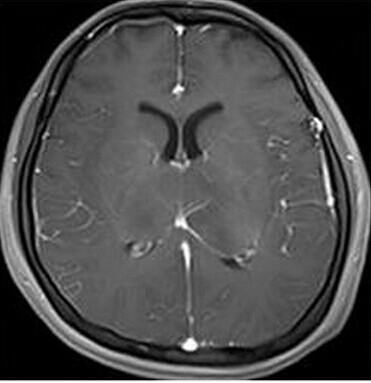

患者:女,23岁,主因嗜睡、言语不利三个月,四肢无力、吞咽障碍3个月入院。

【正确答案】D 大脑胶质瘤病

大脑胶质瘤病的特征性影像学表现是:

(1)肿瘤常累及2-3个脑叶,白质改变为主,占位效应不明显或轻度占位效应;

(2)病变区大脑结构相对保留;

(3)增强后多无强化。